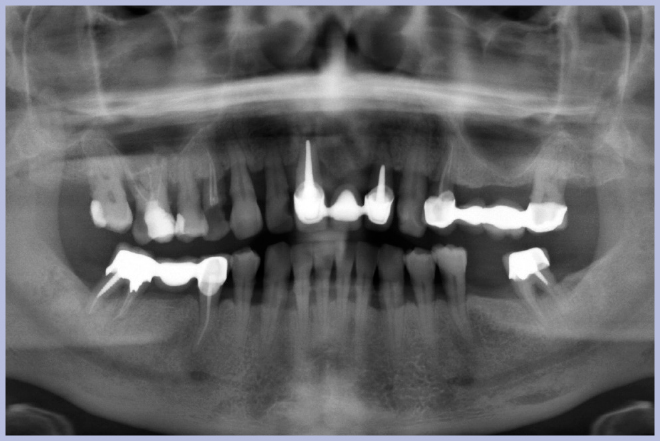

La paziente di anni 55, fumatrice, si presenta con un ponte anteriore in metallo-ceramica (Fig. 1). All’esame clinico il ponte presenta una lieve mobilità ed è evidente la retrazione gengivale con conseguente riassorbimento osseo. Radiologicamente si evidenziano lesioni parodontali, è comunque presente una buona quota ossea sulla quale è possibile inserire un impianto (Fig. 2).

- Fig. 2 – OPT iniziale